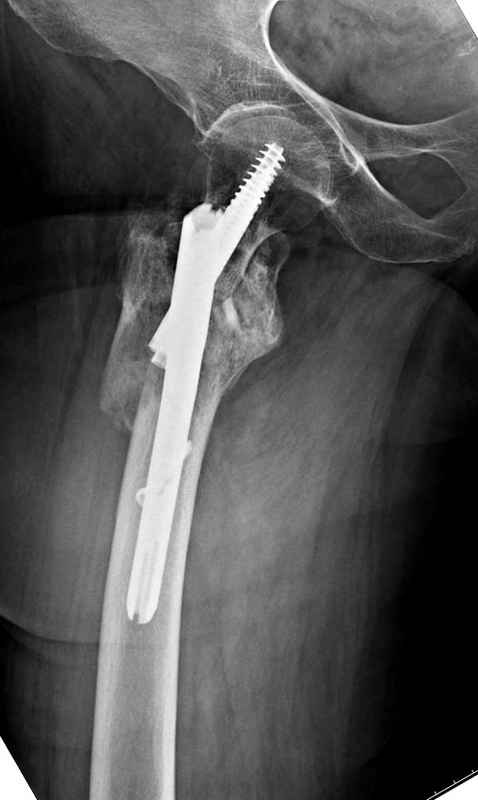

Здесь пара случаев фиксации похожих переломов:

первый высокоэнергетическая травма 36 лет